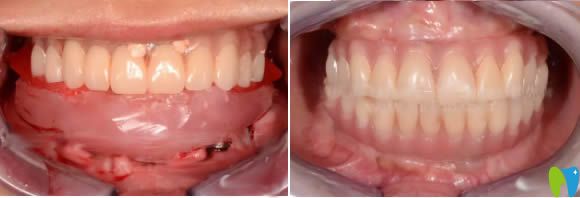

下圖是我剛做完上頜種植牙和下頜牙的即刻效果:

剛做完種牙手術(shù),宏康口腔科的李敬醫(yī)生給我開(kāi)了一些消炎藥,大概要吃3天左右,還給我詳細(xì)叮囑了種植牙術(shù)后注意事項(xiàng),說(shuō)術(shù)后兩天不讓喝熱的東西,48小時(shí)可以使用冰敷袋.....覺(jué)得這個(gè)醫(yī)生負(fù)責(zé)任的。